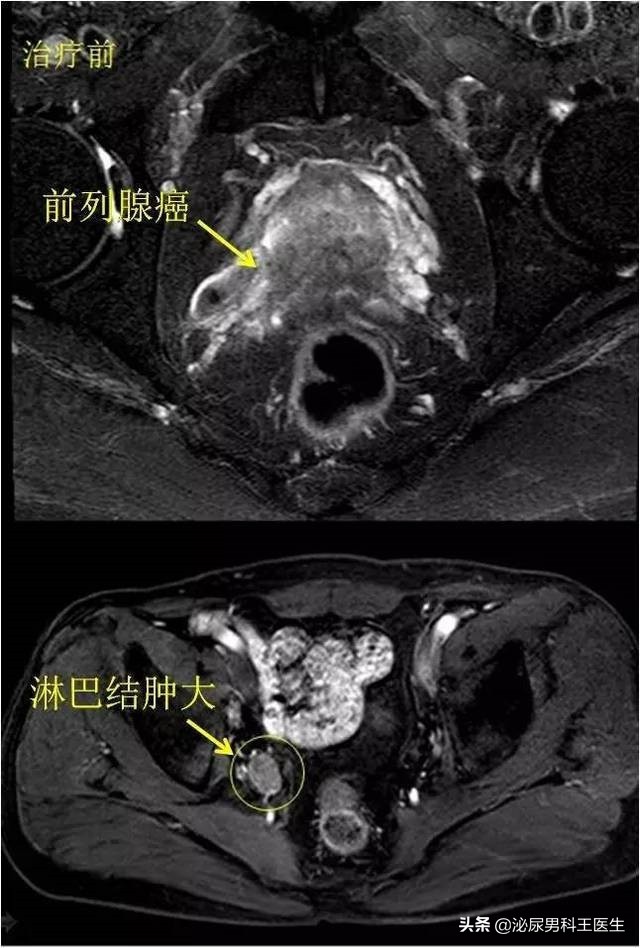

我们先让老严做了一个初步的前列腺特异抗原PSA和肛门的指诊。我们通过一个初步的指诊,摸到了一个包块,疑似前列腺癌。我们又给老严预约了一个核磁检查,他的影像学结果显示前列腺癌有肿块。

有前列腺5.2 cm×5.0 cm×4.0 cm大小,包膜欠光整,多个 1 cm结节 ,并向膀胱内突出2.5 cm。为进一步诊断老严的病况,老严完成了前列腺特异性抗原值的测量, 老严的PSA显示52g/L 。前列腺癌的最终诊断,是需要穿刺活检。对膀胱镜下前列腺尿道和颈口多点活检,病理结果显示确诊前列腺腺癌。